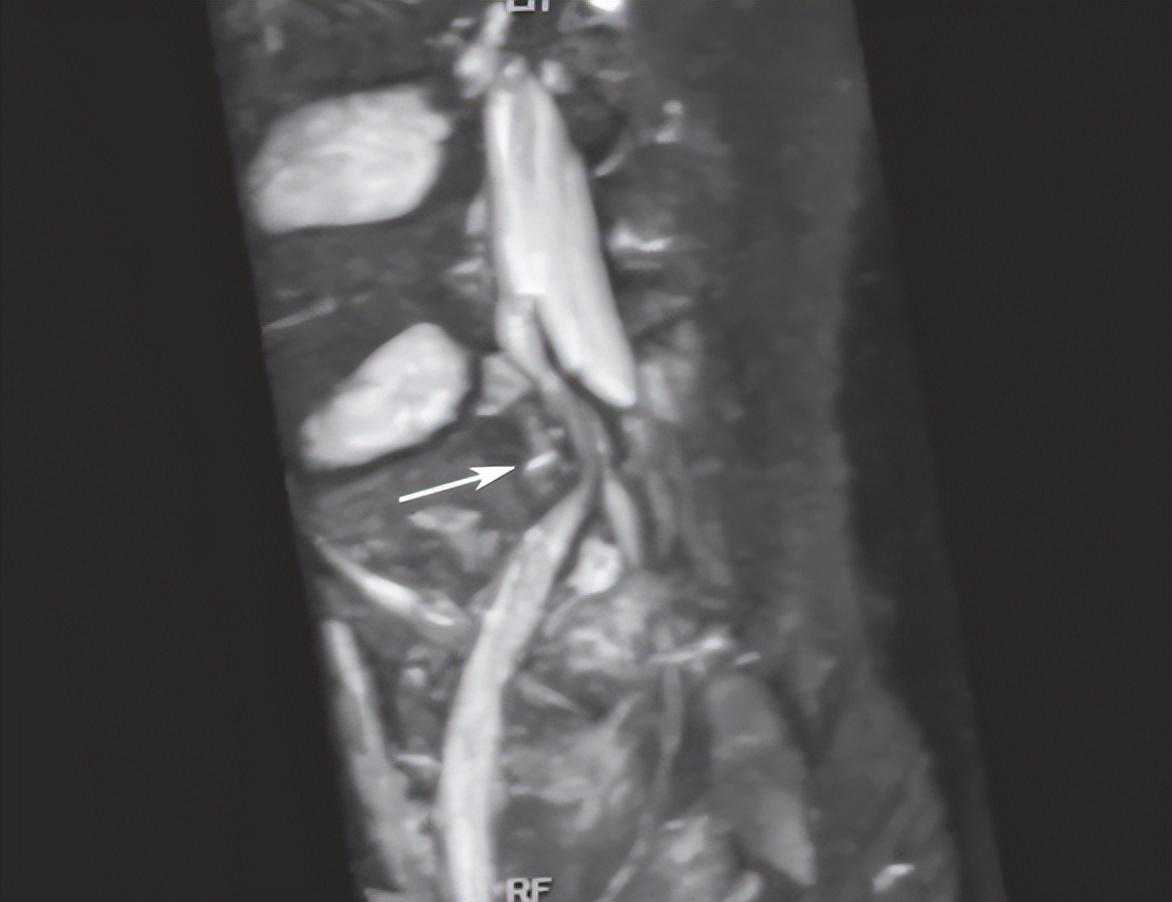

②神经根走行发生改变,是诊断神经根损伤可靠的间接征象,表现为神经根自然走行弧度消失,在骨折处呈弧形受压移位改变,甚至出现成角改变,如图15;

图15右侧骶骨骨折,SPACE-STIR序列MRI神经成像重建可见骨折块自前向后推压S1神经根,神经根自然走行弧度消失,呈弧形移位改变(箭头所指)